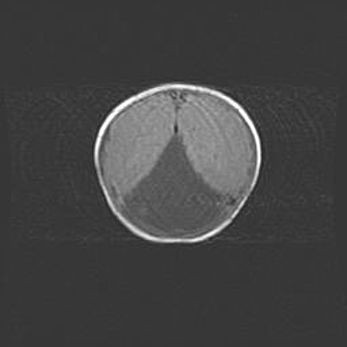

Церебральная ишемия II.

Возраст: 5 дней

Вес: 3400 г

Пол: женский

Окружность головы: 35 см

Срок гестации: 39 недель

Церебральная ишемия – это заболевание, характеризующееся недостаточностью (гипоксией) либо полным прекращением (аноксией) снабжения мозга кислородом по причине закупорки одного или нескольких сосудов. Это приводит к  что метаболическим расстройствам различной степени тяжести в тканях головного мозга, развитию коагуляционных некрозов и гибели нейронов.